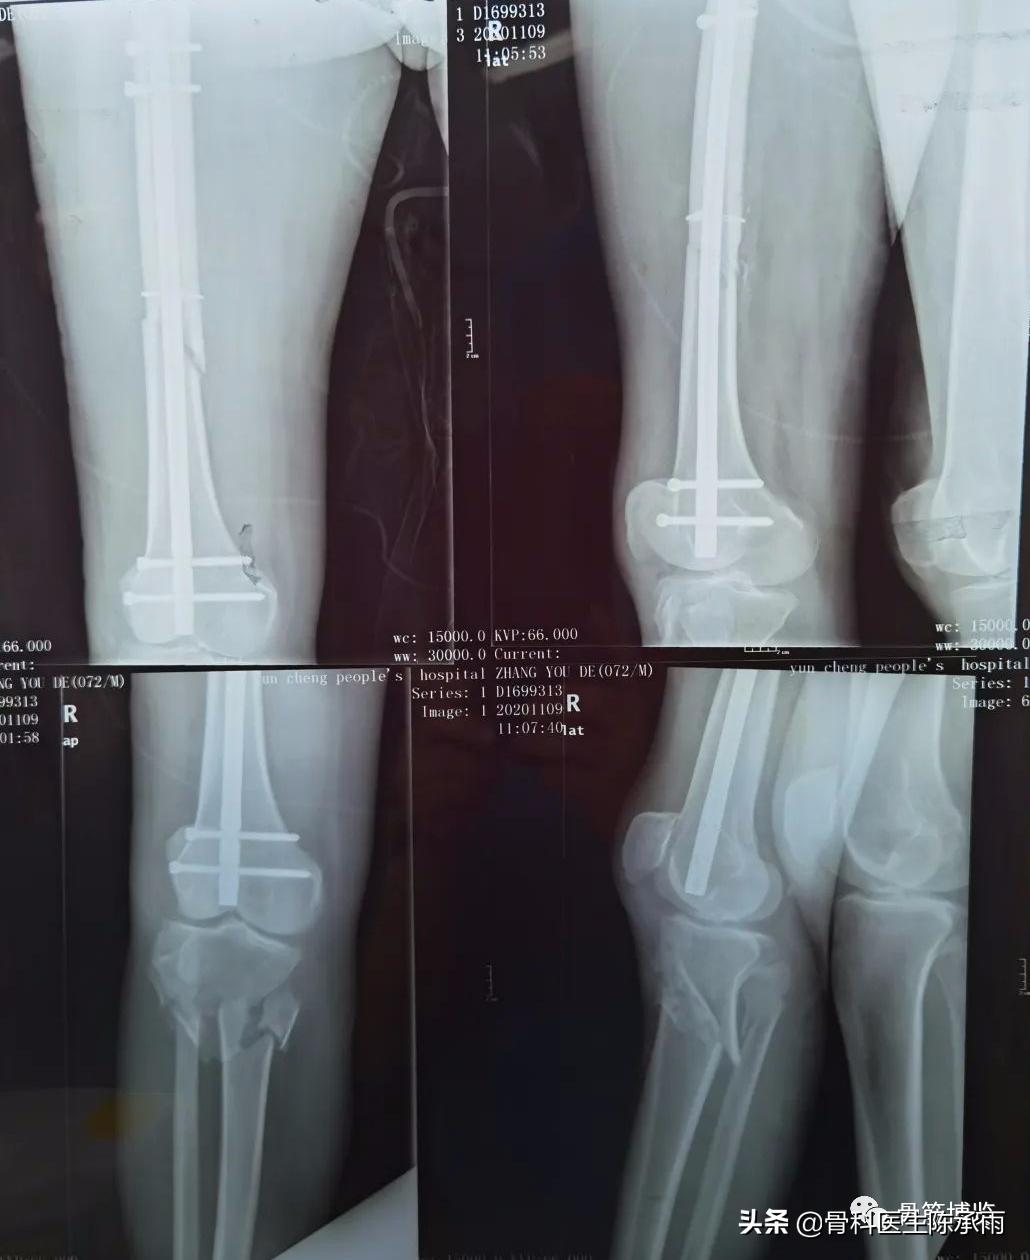

这2例患者皮肤条件差,全身多发骨折,小腿皮肤条件差,1例筋膜高压切开,1例整个小腿布满张力性水泡,胫骨骨折都在伤后30天才能手术。

下例胫平台骨折皮肤条件差,内侧板取两端小切口置入内板固定。胫骨结节处撕脱骨折以1枚拉力螺钉固定。